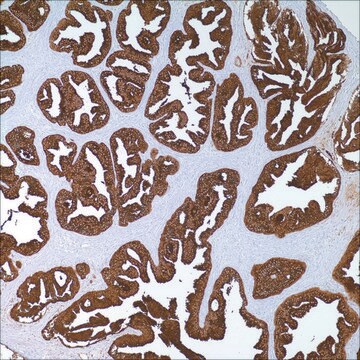

prostate

Prostate-Specific Antigen (PSA) is a 33 kDa protein primarily produced by the prostatic epithelium and the epithelial lining of the periurethral glands . PSA is strongly expressed in both normal and neoplastic prostatic tissue. Although PSA can be considered prostate-specific, PSA and/or PSA gene expression has been detected at low levels in some extra-prostatic tissues such as normal breast tissue, breast tumors, endometrium, adrenal neoplasms and renal cell carcinomas. Anti-PSA is most useful in determining the prostatic origin of carcinomas in non-prostate tissues (metastatic disease) using IHC techniques. This product is best used in conjunction with a panel of antibodies as, up to 27% of prostate carcinoma cases (predominantly poorly differentiated carcinomas) can be negative for this marker.

PSA Positive Control Slides, Product No. 324S, are available for immunohistochemistry (formalin-fixed, paraffin-embedded sections).